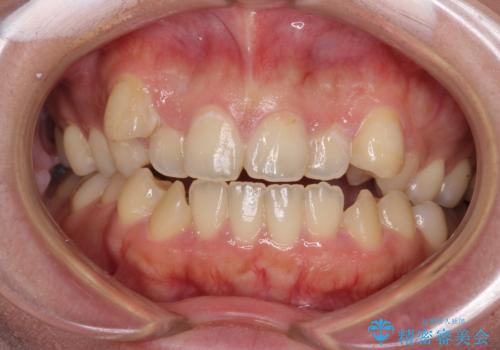

八重歯を抜歯矯正でスッキリと メタルブラケットでの矯正治療

八重歯で口元が膨れている ワイヤー装置での抜歯矯正

重度のガタガタと出っ歯をワイヤーによる抜歯矯正で整った歯並びへ

八重歯をインビザラインで非抜歯矯正